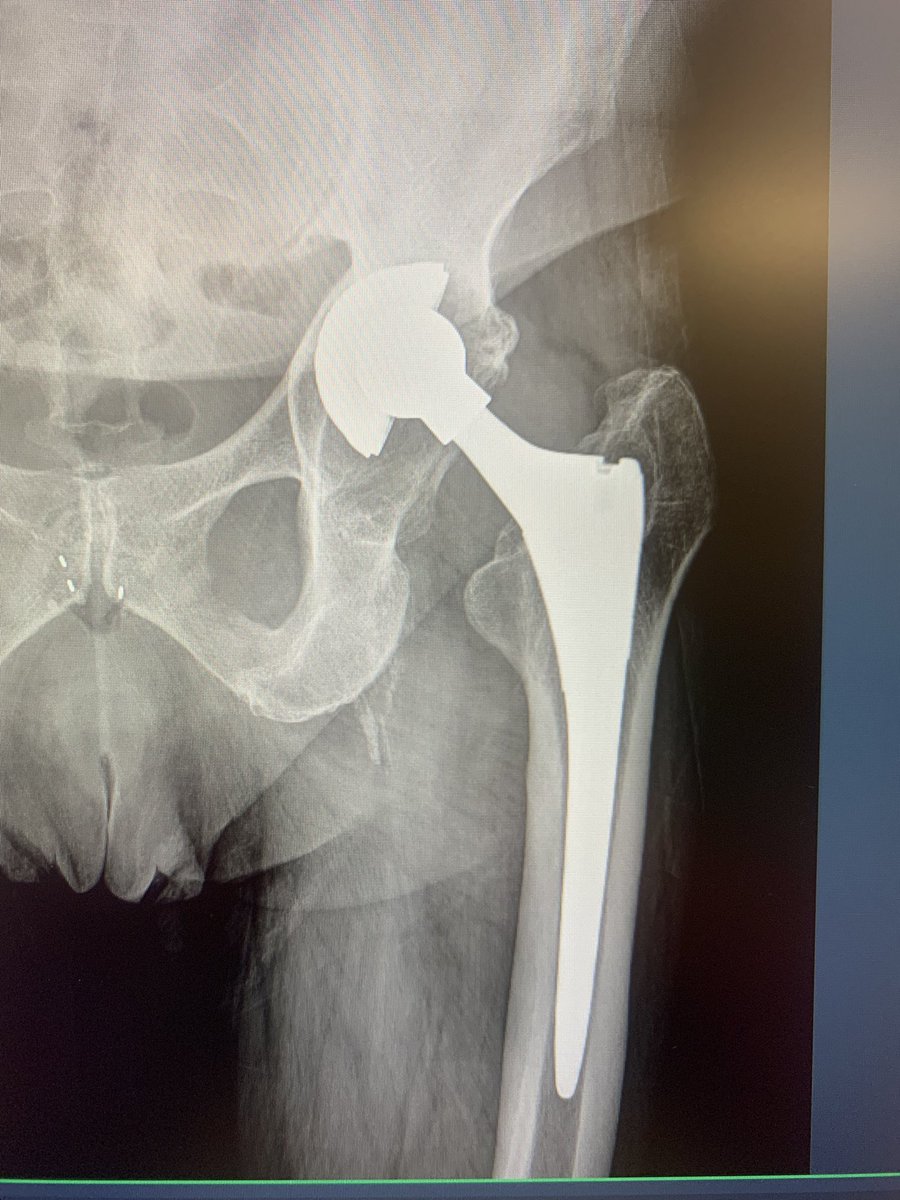

Recently used navigation for the first time in hip revision. #orthotwitter

@generalorthomd @HipReplacement @intellijoint @DeviceNation @NaanDerthaal @jointdocShields